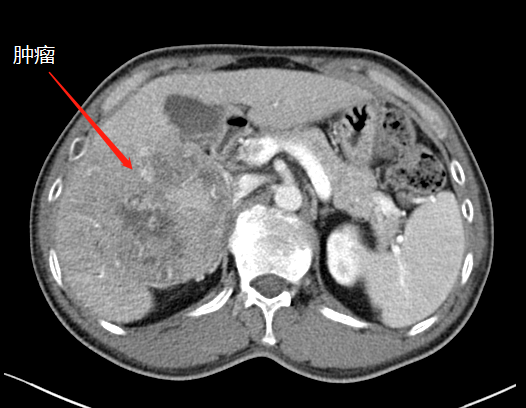

第一次術后,結扎門靜脈劈開肝臟

左肝增生,第二次手術切除腫瘤

“9月底,在第一階段手術中,我們先將患者的右側門靜脈結扎(肝的血液供應通過門靜脈和肝動脈進行),保留肝動脈、肝靜脈和膽管的完整性,然后沿肝中裂將肝臟的左右葉徹底劈開?!睋鷤ソ榻B,人體肝臟具有很強的再生功能,結扎門靜脈右支后左側肝臟由于過量的血液供應短期內迅速增大;同時將患者的左右肝臟離斷,降低了腫瘤侵犯左側肝臟的可能。

第一次手術后

經過20天左右的“養(yǎng)肝”,經CT復查顯示,患者的左側肝臟體積已增長至42.8%,這時候,也就達到了我們說的“養(yǎng)大好肝、再切病肝”,因為此時好肝已經足以維持患者身體的運轉需要。